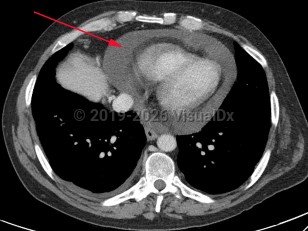

Cardiac tamponadeCardiac tamponade

Pericardial effusionPericardial effusion